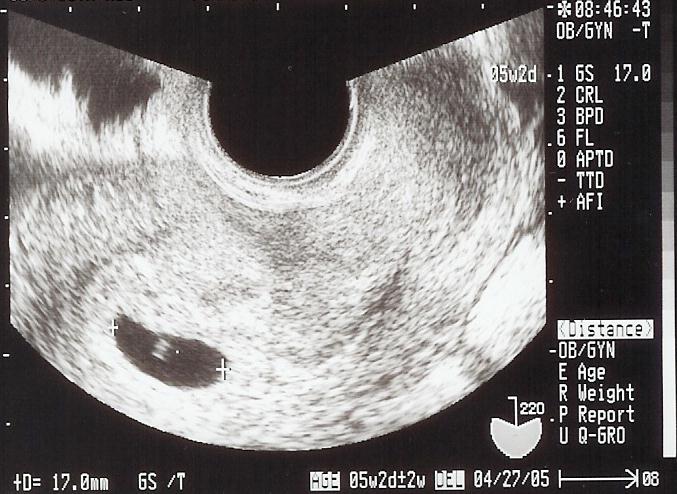

5週2日

shigeruは無事でした!

左下の黒くなっているところが袋で、shigeruは真ん中の白い影(見えるかな)だよ。袋が17ミリしかないから、まだまだ米粒だね。